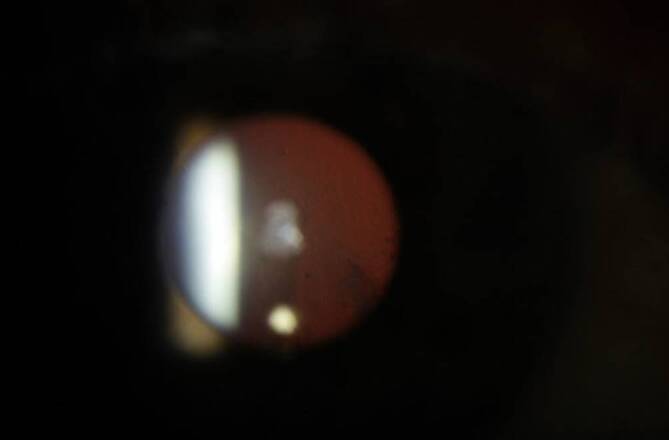

In der Untersuchung zeigte sich eine rechtsseitige Hyperopisierung mit einem rechtsseitigen Visus von 0,6 (Sphäre (S) +2,50 Zylinder (Z) −1,50 Achse (A) 14) und einem linksseitigen Visus von 0,8 (S −2,75 Z 0 A 0). Der intraokulare Druck war beidseits normoton. Rechtsseitig zeigte sich eine hintere Kapseltrübung mit Verdacht auf einen Kapselriss bei 4 und 8 Uhr bei einem sonst unauffälligen vorderen Augenabschnitt (Abb. 1). Linksseitig zeigte sich ein unauffälliger vorderer Augenabschnitt. Die Fundoskopie ergab beidseits einen unauffälligen Befund. Die Abb. 2 zeigt eine Scheimpflug-Tomographie-Aufnahme mit Darstellung des Hinterkapseldefekts.